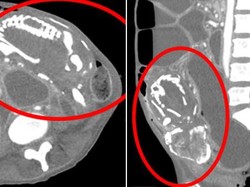

Wanita Meninggal Kekurangan Gizi, Janin 9 Tahun Ditemukan Bersarang di Perut

Seorang wanita berusia 50 tahun meninggal karena kekurangan gizi. Penyakit langkah "bayi batu" di dalam perut menjadi pemicu kekurangan gizi.